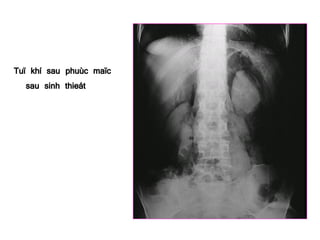

Tuï khí sau phuùc maïc

sau sinh thieát